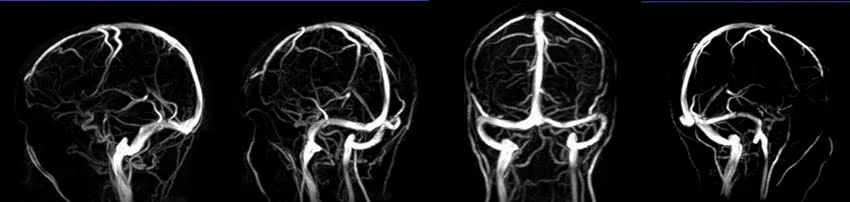

3D PHASE CONTRAST( PC) SEQUENCE USED IN MRV BRAIN IMAGING

POST PROCESSED MIP IMAGES